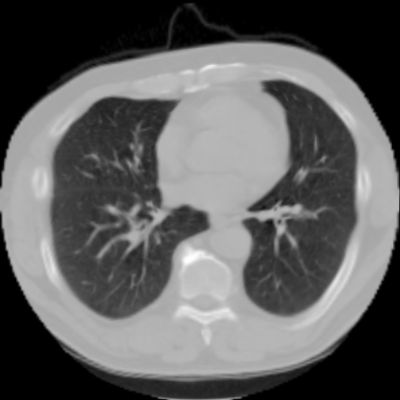

7.3. Real CT images

We now consider applying the proposed image registration method on real lung CT images retrieved from the National Lung Screening Trial (NLST) dataset [1]. Fig. 9(a) and Fig. 9(b) show two slices of lung CT images that we use as the source and the target (see Fig. 9(c) for the absolute intensity difference). We remark that the CT images are originally with different intensity, and so we apply an intensity histogram matching before running the registration experiment. Fig. 9(d) shows the registration result obtained by our proposed method. It can be observed that our method successfully produces a large deformation on the right lung of the source image to match that of the target image (see also Fig. 9(e) for the final absolute intensity difference). On the contrary, DDemons [47] (Fig. 9(f)), LDDMM [5] (Fig. 9(g)), Elastix [29] (Fig. 9(h)) and DROP [18] (Fig. 9(i)) all fail to produce an accurate and bijective registration result. This shows that our method is more capable of handling large deformation image registration.